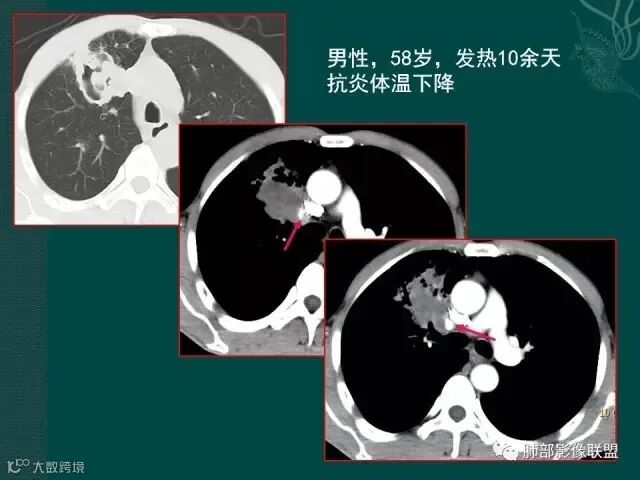

病史似乎是炎性;空洞型病变,靠近纵隔的时候,一定要看对纵隔是否有侵蚀,这是相当重要的。

红箭头所指是右上肺静脉,起始部是完好的,上一层被病变完全包埋,管腔变窄,管壁形态不规则,并侵犯相邻纵隔。

肺癌靠近纵隔时,对纵隔的侵犯,对诊断有重要诊断价值,炎症的话很少会侵犯血管。